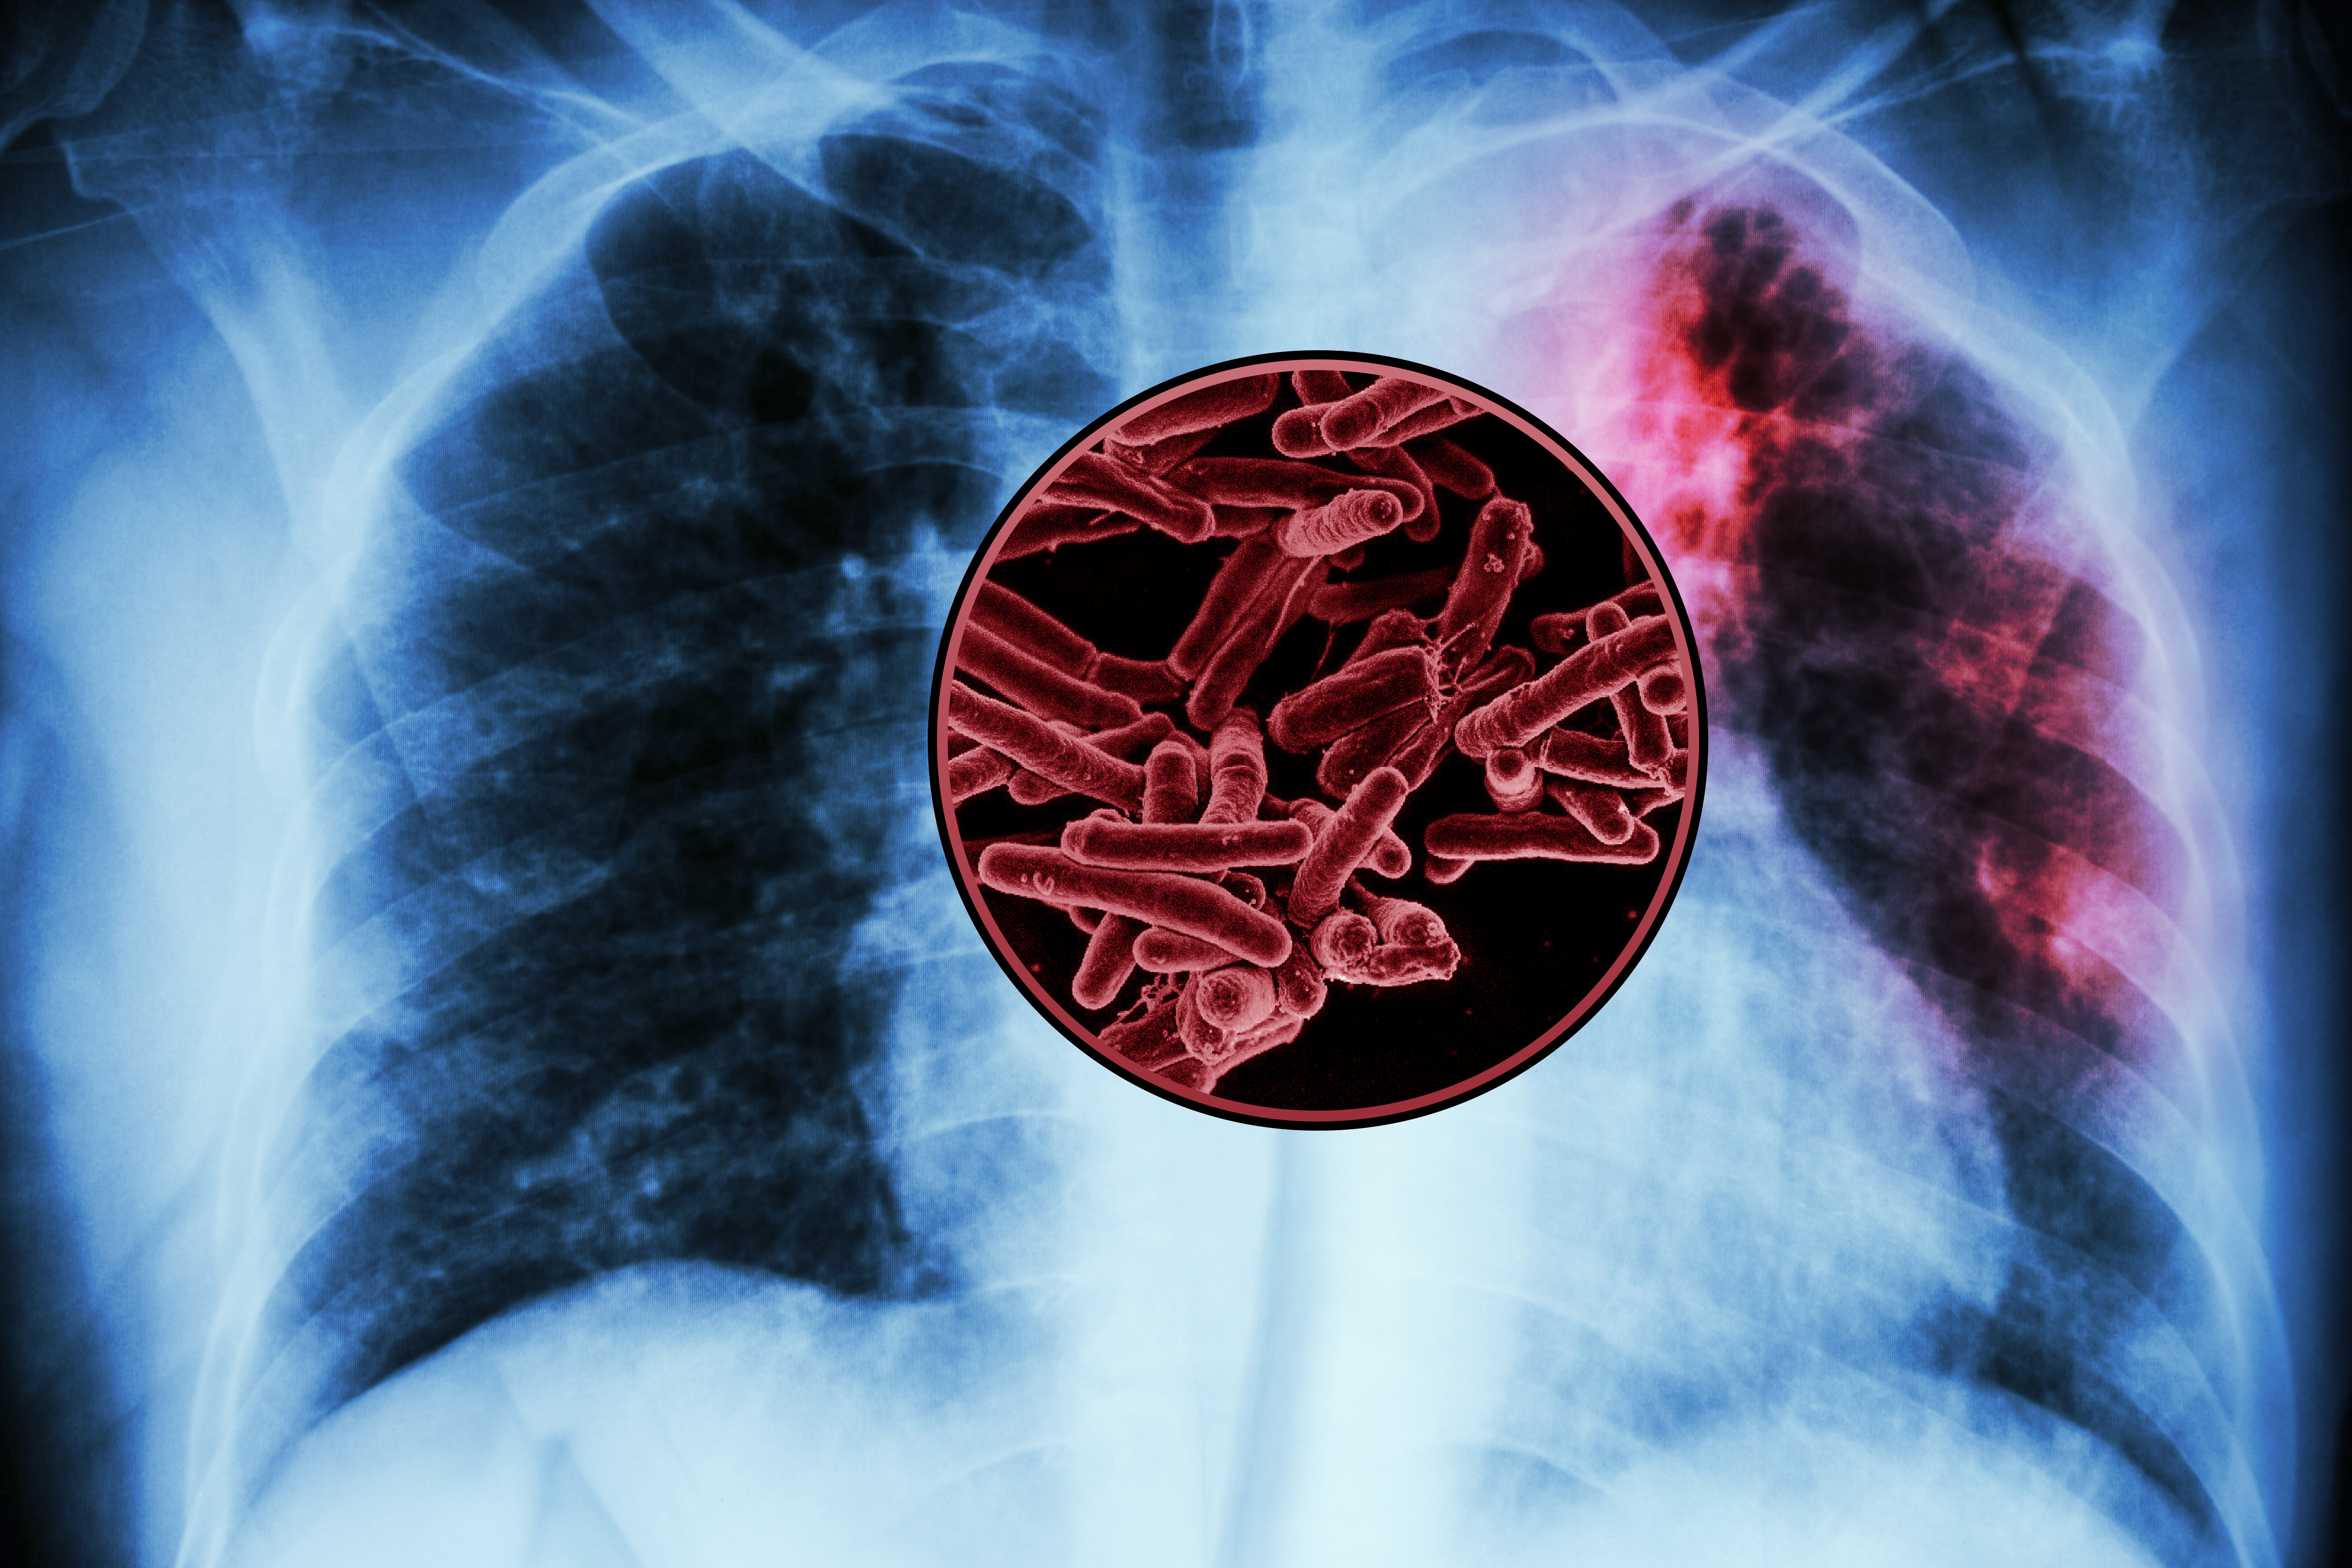

MIT study finds targets for a new tuberculosis vaccine

Using these antigens, researchers plan to develop vaccine candidates that they hope would stimulate a strong immune response against the world’s deadliest pathogen.